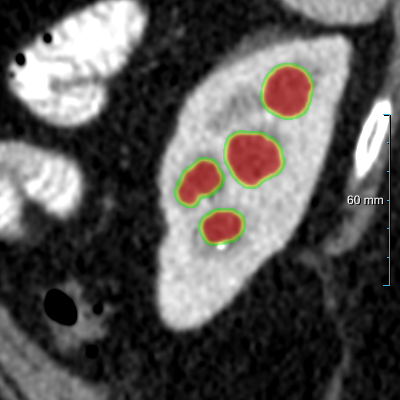

Figure 3: Four examples of CT scans from the training set (dataset A) showing coronal sections with annotations in format 2 (see Figure 2(c)) where yellow and red overlays represent annotations of the parenchyma and kidney abnormalities, respectively. Note that all the patients have anomalies in the body (green arrows in the body), and both cases of (b) have only one kidney and contain kidney abnormalities. All the slices have a window center of 60 HU and a window width of 360 HU.

Samples of CT scans from patients included in this study can be seen in Figure 3. While Figure 3(a) depicts patients without kidney abnormalities, it highlights the presence of abnormalities in other parts of the body, such as liver tumors. Figure 3(b) shows patients with kidney abnormalities, as well as other abnormalities in the body, such as nephrectomy and collapsed lung.